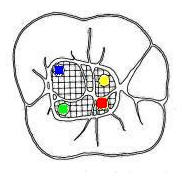

Cuarto conducto en molares inferiores (Color amarillo)

Cuando tiene tres conductos el mas amplio es el distal con una sección oval y su curvatura es suave o recta. Si presenta cuatro conductos la raíz distal contendrá dos de ellos y son de diámetro más pequeño y en caso de presentar dos conductos, ambos son amplios.